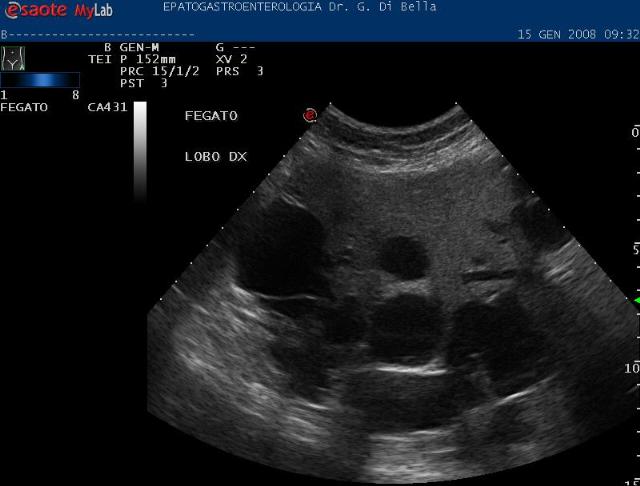

Studio Medico Dott Di Bella Gastroenterologo Centro Medico Specializzato In Epatogastoenterologia E Nutrizione